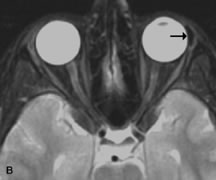

On MRI, uveal melanomas have a typical appearance that helps to differentiate them from other primary and secondary intraocular tumors as well as choroidal detachments. Pigmented melanomas are hyperintense on Tl-weighted images, hypointense on T2-weighted studies, and hyperintense on proton density–weighted examinations (Fig. 24).30,31,50,80–82 These signal characteristics have been attributed to the paramagnetic properties of melanin because of stable free radicals that shorten the T1 and T2 relaxation times. Moderate enhancement is seen on postgadolinium T2-weighted images. Gadolinium-enhanced T1-weighted images are particularly sensitive in detecting choroidal melanomas.83 MRI may be less sensitive in detecting extrascleral extension of tumor than echography performed by an experienced ultrasonographer.84

Fig. 24. A. T1- and (B) T2-weighted MR scans demonstrate a small nodular intraocular mass (arrows) that is very hyperintense on the T1-weighted scan and hypointense on the T2-weighted image. This signal intensity pattern is due to the presence of free radicals within melanin granules. C and D. Postcontrast fat-suppressed T1-weighted scans demonstrate homogeneous intense enhancement of the lesion and no evidence of seleral penetration or optic nerve invasion.